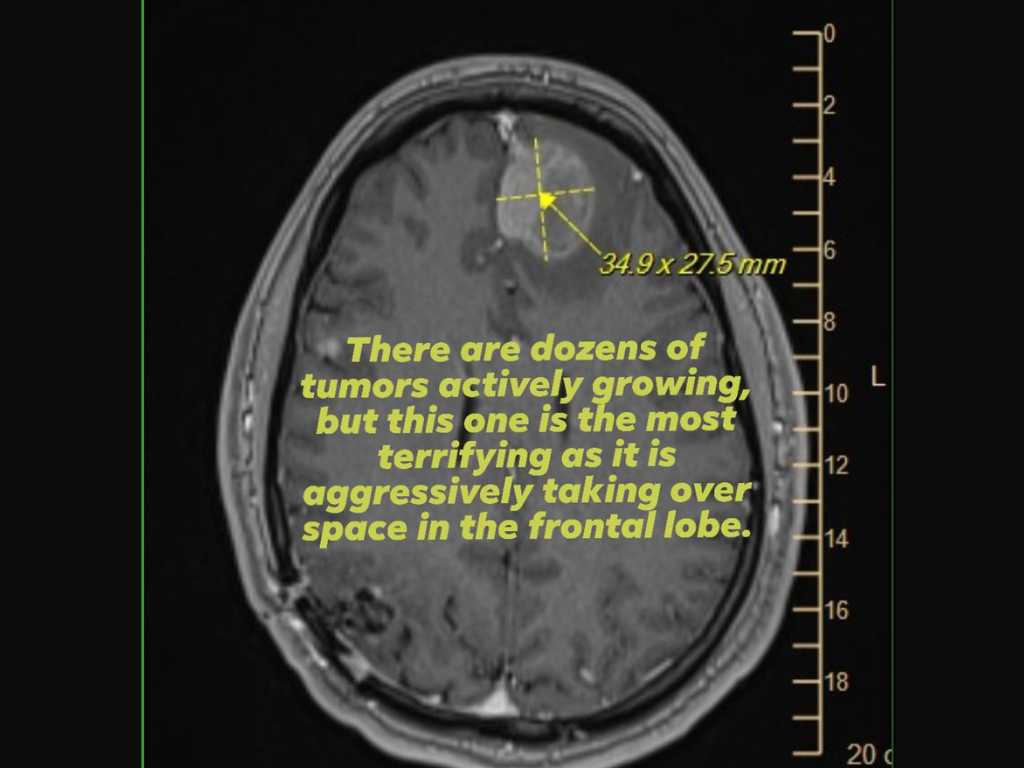

Som bevis bifogade hon också en bild av en hjärnscanning (MRI) som visade en aggressiv tumör i frontalloben medan hon vädjade om stöd eller hjälp från cheferna på Epic Games, som fattade de viktigaste besluten om uppsägningarna.